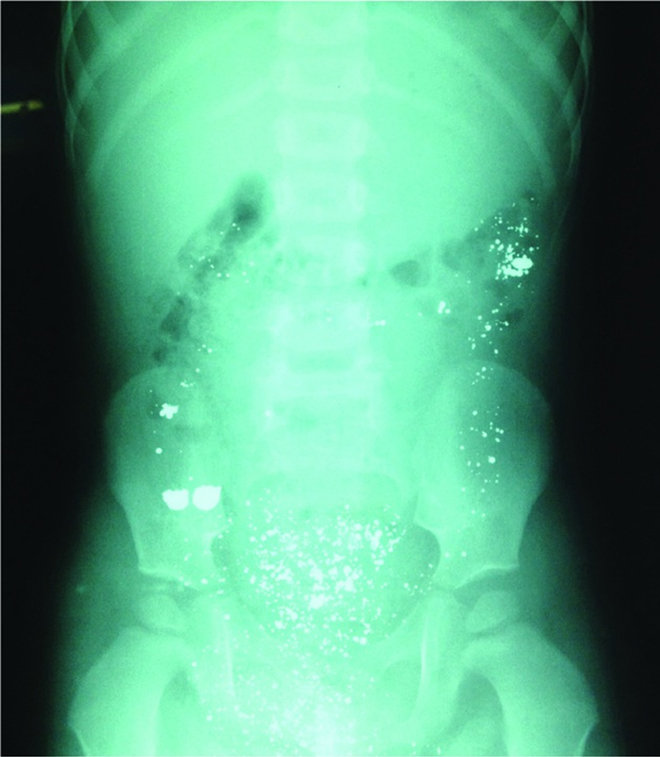

Hình ảnh X-quang bụng cháu bé ngày đầu tiên khi uống nhầm thủy ngân

Và sau 7 ngày cho thấy lượng thủy ngân đã được đào thải hết ra ngoài.